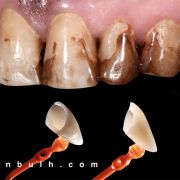

The patient was complaining of heavy stain and multiple faulty restorations. Considering the age in analyzing the teeth shape, contour and color play a vital role in success. Root canal treatment was done for the anterior teeth (Dr Khalid Merdad). Veneers and crowns @perlasmile lab.